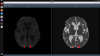

DeepISLES is an advanced tool designed for the segmentation of ischemic stroke lesions in MRI. It accurately identifies and segments infarctions across various brain regions, encompassing a wide spectrum of sizes, ischemia counts, and patterns. Developed as part of the ISLES 2022 challenge, the algorithm operates on DWI, ADC, and optionally, FLAIR images.